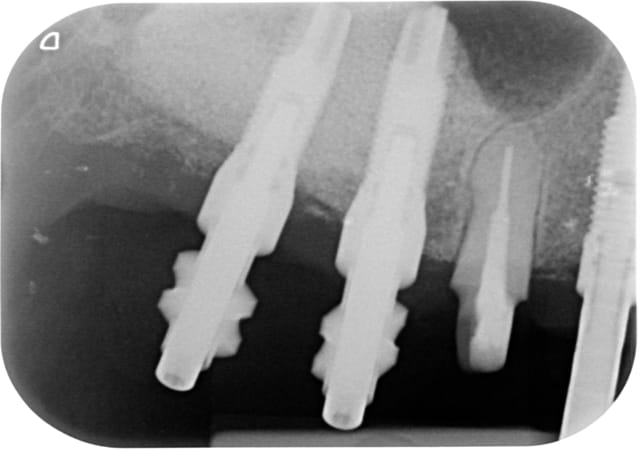

07/11/2014 à 10h08

Photo des moulages de face en occlusion ?

Pas encore réfléchi mais ça m a bien l air occlusal ton affaire.....

07/11/2014 à 13h22

Tiens mon lapin!

En effet que le point de contact fort entre deux implants la chassée en apical.

Dsc 8424 imuo3z - Eugenol